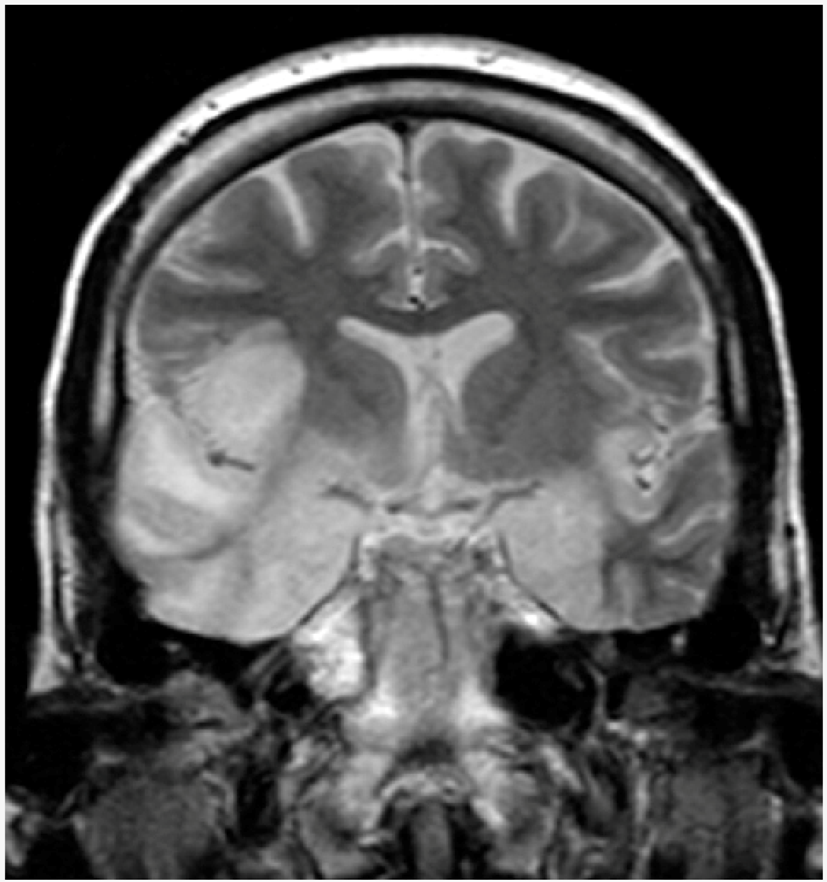

There are two types of herpes simplex virus, type 1 (HSV-1) and type 2 (HSV-2). HSV-1 most commonly causes oral infections while HSV-2 most commonly affects the genitals. They are transmitted by direct contact with body fluids or through injuries to an infected individual. Transmission may also occur when symptoms are not present. Genital herpes is classified as a sexually transmitted disease. During delivery, herpes simplex can be transmitted to the baby. After infection, the viruses are transported along the sensory nerves to the bodies of nerve cells. The causes of recurrence can include decreased immune function, stress and exposure to the sun. Cold and genital herpes are usually diagnosed based on the presentation of symptoms. Diagnosis can be confirmed by viral culture or detection of herpes DNA in urine. Blood tests in search of antibodies against the virus may confirm a previous infection. The most effective way to avoid genital infections is to avoid vaginal, oral and anal sex. The use of condoms slightly decreases the risk. The daily intake of an antiviral drug by the infected person may reduce the spread. There is no vaccine available and, once infected, there is no cure. Paracetamol and topical lidocaine can be used to relieve symptoms. Treatments with antiviral drugs such as acyclovir or valaciclovir can reduce the severity of symptomatic episodes. Globally, rates among HSV-1 or HSV-2 adults are between 60% and 95%. HSV-1 is usually acquired during childhood. The incidence of HSV-1 is between 70% and 80% in populations of low socio-economic status and between 40% and 60% in those with a higher status. HSV infections cause several distinct medical disorders. Common infections of the skin or mucous membranes can affect the face and mouth (orofacial herpes), genital organs (genital herpes) or on the hands (herpetic fever). More serious disorders occur when the virus infects the eye (herpes keratitis) or invades the central nervous system, damaging the brain (herpetic encephalitis). People with immature or suppressed immune systems, such as newborns, transplant recipients or people with AIDS, are prone to get serious complications from HSV infections. These infections are also associated with cognitive deficits in bipolar disorder and Alzheimer’s disease, although this often depends on the genetics of the infected person. The spread of pathogens from the oral environment to the brain has recently been reported [21]. In all cases, HSV is never removed from the body by the immune system.